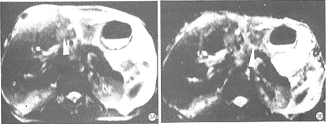

图4 肝右叶下段多发小HCC。A.HASTE-T2WI示外侧缘小病灶呈高信号,而内侧缘病灶显示欠清,无法确认。B.HASTE-IR-T2WI示

右叶下段2枚小HCC呈不均匀的高信号,边界清晰